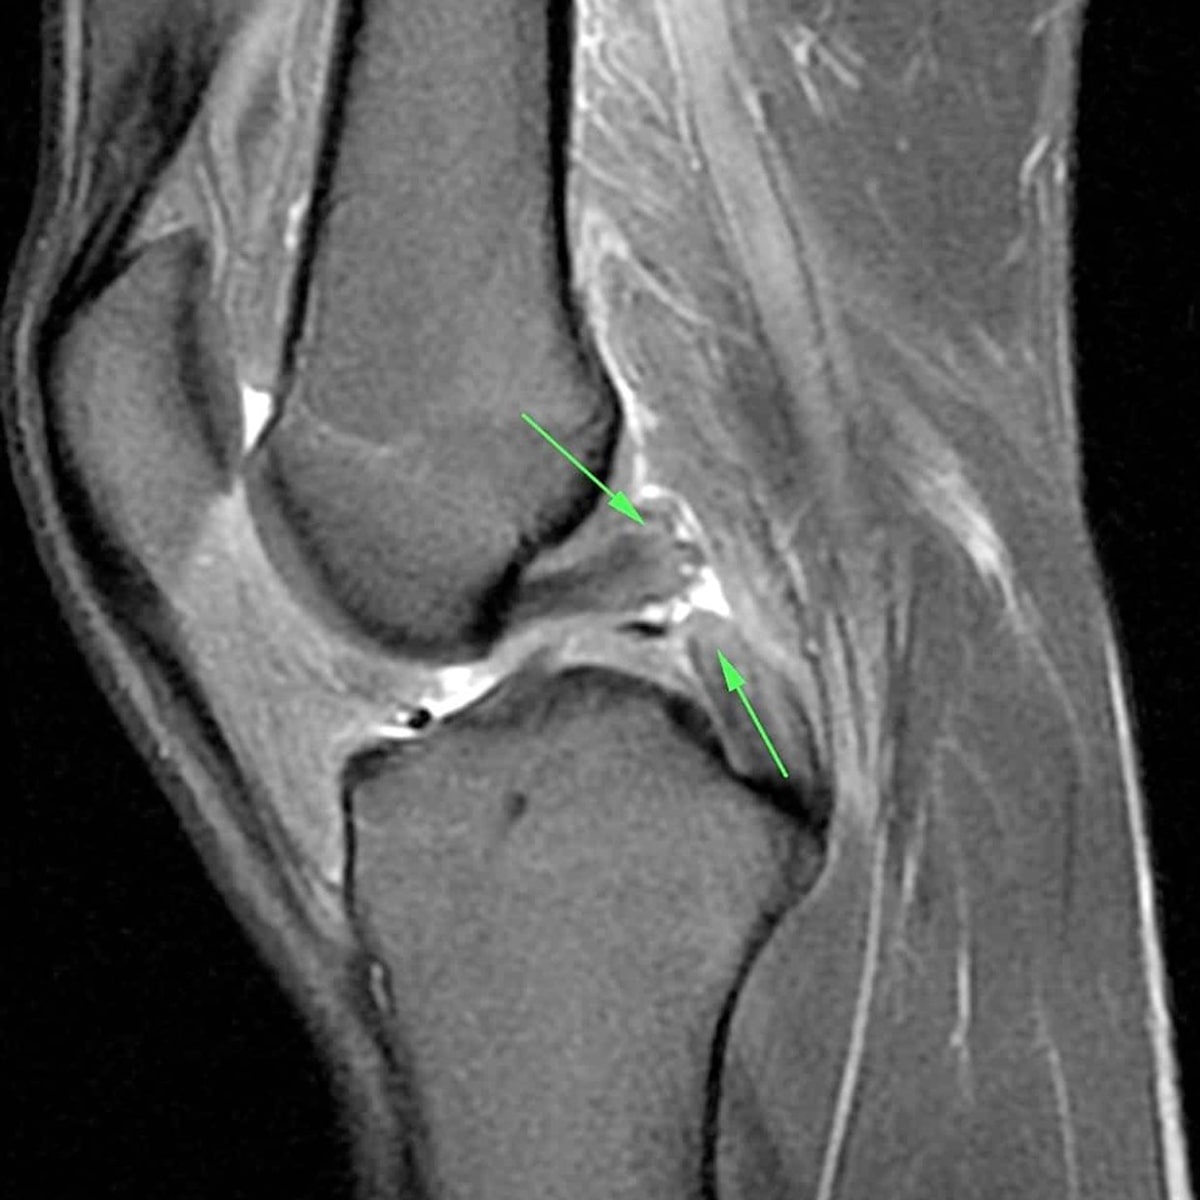

Hinteres Kreuzband

Das hintere Kreuzband (HKB) ist das stärkste Band des Kniegelenks. Seine Aufgabe besteht darin, ein nach hinten Rutschen des Unterschenkels gegenüber dem Oberschenkel zu unterbinden. Eine Verletzung des hinteren Kreuzbandes entsteht bei hohen Krafteinwirkungen wie z. B. bei Fahrrad- und Motorradstürzen auf das gebeugte Knie oder anderen Hochgeschwindigkeitsverletzungen. Im Vergleich zum vorderen Kreuzband sind Verletzungen des hinteren Kreuzbandes seltener, aber auch die am häufigsten übersehene Verletzung im Kniegelenk, was zur Folge hat, dass es oftmals zu einer unzureichenden, gar keiner oder gar falschen Behandlung kommt. Daher haben die ausführliche Anamnese und Diagnose bei der hinteren Kreuzband Verletzung ein besonderes Gewicht.